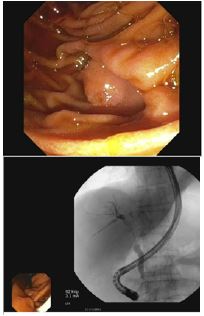

The enhancement characteristics and location were most suspicious for cholangiocarcinoma. The patient was discharged from the hospital and scheduled for Endoscopic Retrograde Cholangiopancreatography (ERCP) the following week. The patient underwent ERCP with Endoscopic Ultrasound (EUS) which demonstrated a 3 cm intraductal hilar mass extending to the right hepatic duct (Figures 2 & 3).

Figure 2 and 3: Presence of 3 cm intraductal hilar mass with positioning shown in reference to the abdomen